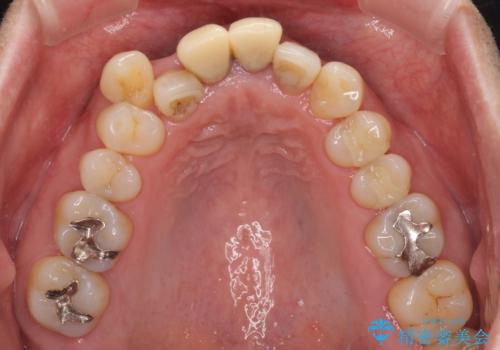

上顎前歯の突出感と右上の八重歯を気にされていたので、上顎左右の第一小臼歯2本を抜歯し、ワイヤー装置にて矯正治療を行うこととしました。

上顎前歯に装着されていた保険診療の前歯は見た目が気になるとのことであったので、矯正治療後にオールセラミッククラウンにて補綴治療を行うこととしました。

食いしばりにより奥歯がすり減っており、咬み合わせが定まるまで時間がかかりましたが、整った口もに仕上がりました。